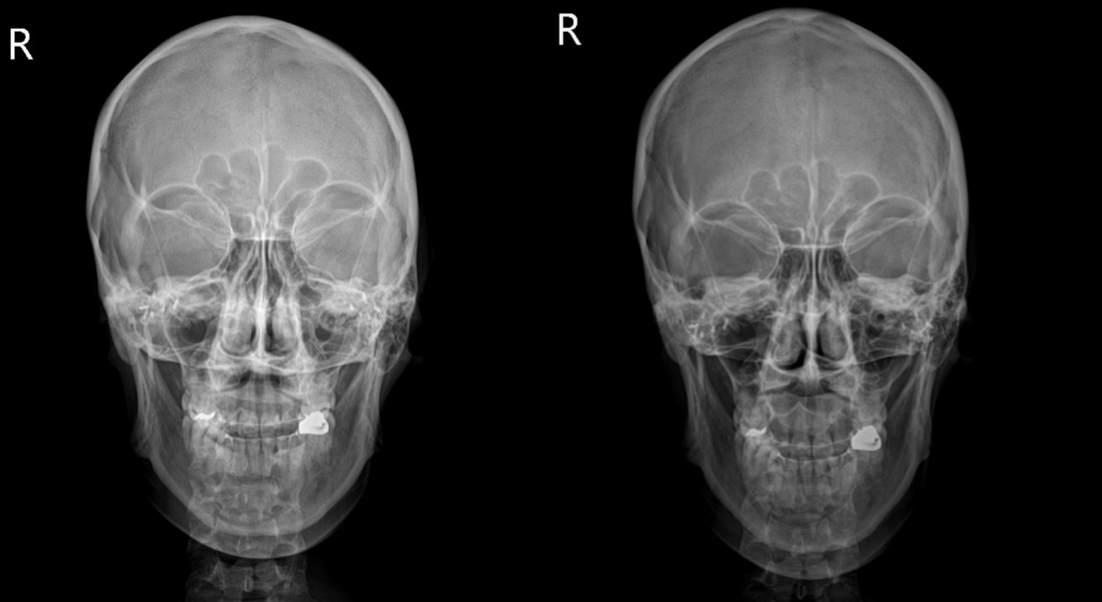

air는 엑스레이에서 까맣게 보여요

위 사진의 두 환자 분의 경우 두개안면골의 비틀림을 재정렬해주는 것만으로도 비중격이 위치가 개선되고 비강 내 공기의 흐름이 좋아진 것을 관찰할 수 있습니다.